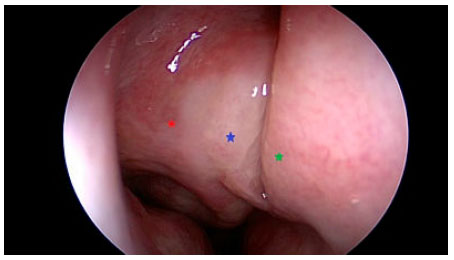

Al examen endoscópico nasal, en la fosa derecha las estructuras intranasales formaban una masa blanda compuesta por cornete medio, bulla etmoidal y proceso uncinado adherida a septum nasal (Figura 2). La fosa nasal izquierda presentó una masa blanda similar, pero de menor tamaño. Los exámenes sanguíneos de rutina estaban dentro de los valores normales.

Figura 2 Vista endoscópica de la cavidad nasal derecha. Desviación septal (estrella verde) adherida a una masa compuesta de cornete medio (estrella azul), bulla etmoidal y proceso uncinado (estrella Roja).